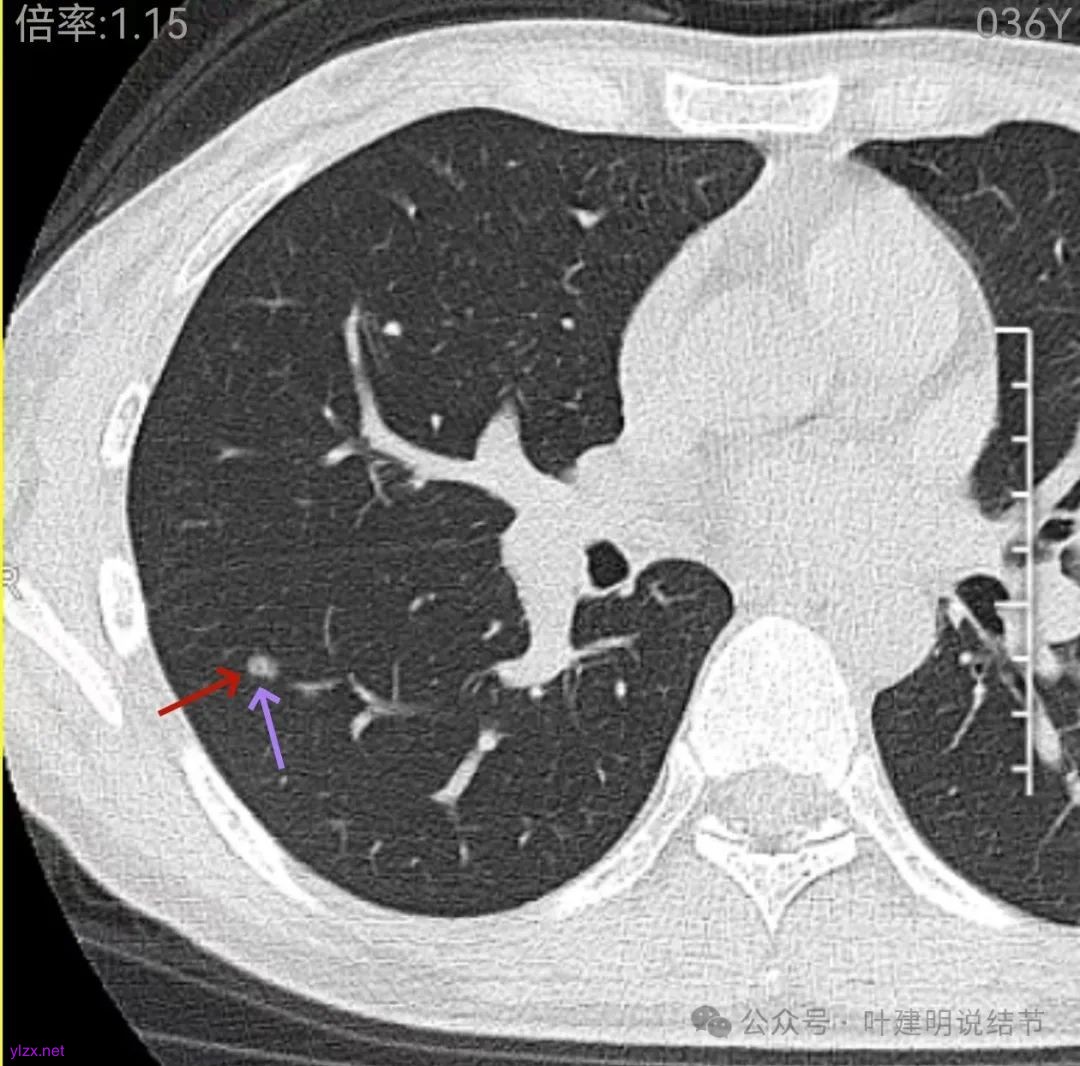

这层面看,密度不纯,部分区域的边缘有细毛刺征。但感觉与前一层面的结节形态不似延续过来的。

边缘区密度也略显高,圆形的样子。

怎么有个点状密度较高的结节在?与上面那截图的淡磨并不完全在一块的。

密度甚高,边界与轮廓清楚,只看这真的不像恶性些。

边缘区也瘤肺界限稍糊,整体轮廓还行。有进展的是不是就是淡磨那处?